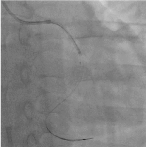

Trans-radial coronary angiogram revealed tortuous and aneurysmal dilatation (ectatic vessels) of all three major coronary arteries (Figure 3a, 3b) with huge thrombus in the proximal segment of left circumflex (LCx) artery, the culprit lesion was identified. Left coronary system was engaged with XB 3.0 6-French guiding catheter through right radial access with 6F sheath. The lesion was crossed by Run through NS floppy (Terumo) hydrophilic 0.014 inches wire. Among different strategies to deal with huge thrombus burden such as Plain Old Balloon Angioplasty (POBA), thrombus aspiration and intracoronary glycoprotein IIb/IIIa inhibitor, we proceeded with thrombus aspiration. Thrombuster II (Kaneka Corporation) thrombus aspiration catheter introduced into the target vessel and suctioning performed. Blood clots aspirated as shown (Figure 4). After few aspirations, failed to do further suctioning and planned to flush as the catheter may get blocked from aspirated thrombus. Some degree of resistance was felt while removing the catheter from the vessel. The thrombus aspiration catheter finally came out with slight pulling force but noted that the tip was missing (Figure 5). Angiographically, the tip of Thrombuster II catheter seen attached to the guidewire (Figure 6). The guidewire can move freely along the mid and distal LCx but failed to withdrawal at the proximal LCx area.

Figure 3a. Left coronary artery Figure 3b. Right coronary artery